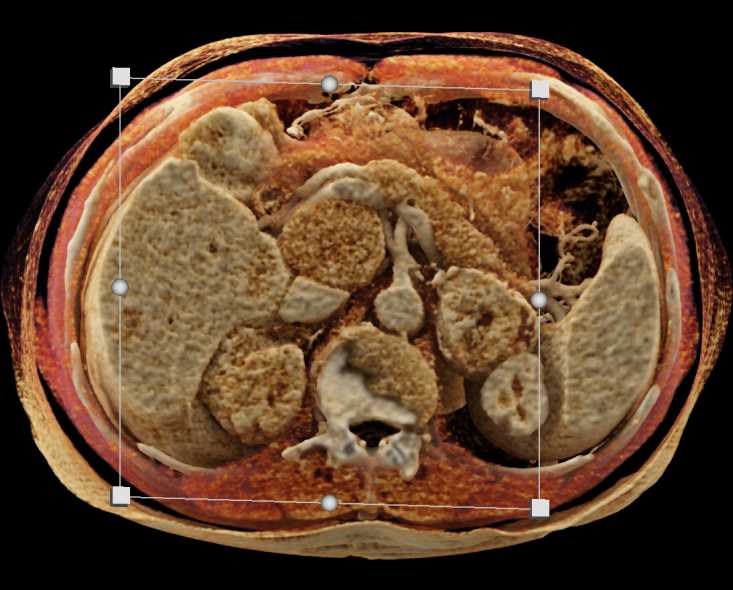

Left Adrenal Metastases from Renal Cell Carcinoma